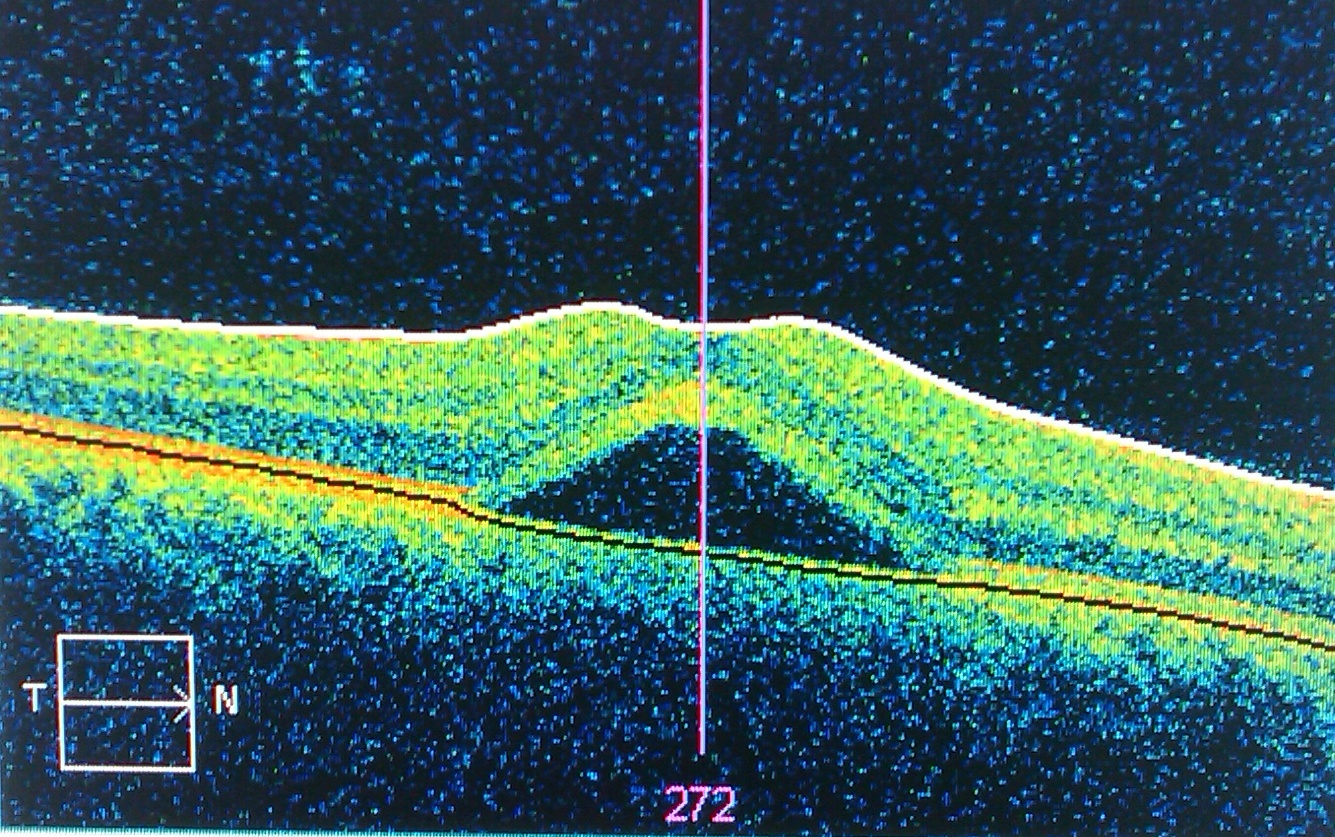

As a biologist, a Cell paper can be the highlight of one’s career. Cell publishes the best work from across all fields of biology, and the Kermany et. al. paper from last year represented a breakthrough in applying deep learning to ocular pathology. Briefly, they used an imaging technology called retinal optical coherence tomography (OCT) to image healthy and diseased eyes (3 possible conditions) and employed a panel of expert pathologists to classify them. They had multiple pathologists classify a subset of photos so they could get a measure of how accurate the humans were as well.

We’re trying to classify the eyes into one of 4 categories. 1. Healthy 2. Choroidal Neovascularization (blood vessel formation in the eye, related to macular degeneration) 3. Diabetic macular edema (fluid in the retina) 4. Drusen (fat deposits in the retina)

Moving forward, it has been shown that medical imaging models are highly sensitive to the instrumentation and hospital where the images were generated (ref). I’m working with a friend at Baylor Medical Center to gather an additional set of OCT images as a test set to compare the two models with data from an unrelated institution. The results of that experiment will be a good test for both models and I’ll be sure to provide an update.